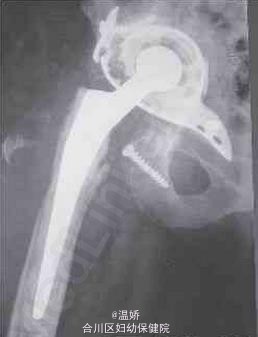

全髋关节置换翻修术后周围血管肉瘤

温医师   重庆市合川区妇幼保健院

患者为84岁女性,因右髋关节疼痛入院。在过去的数月中,疼痛逐渐加重,活动明显受限。近来其疼痛、关节僵硬度以及右髋周围发热情况加重。